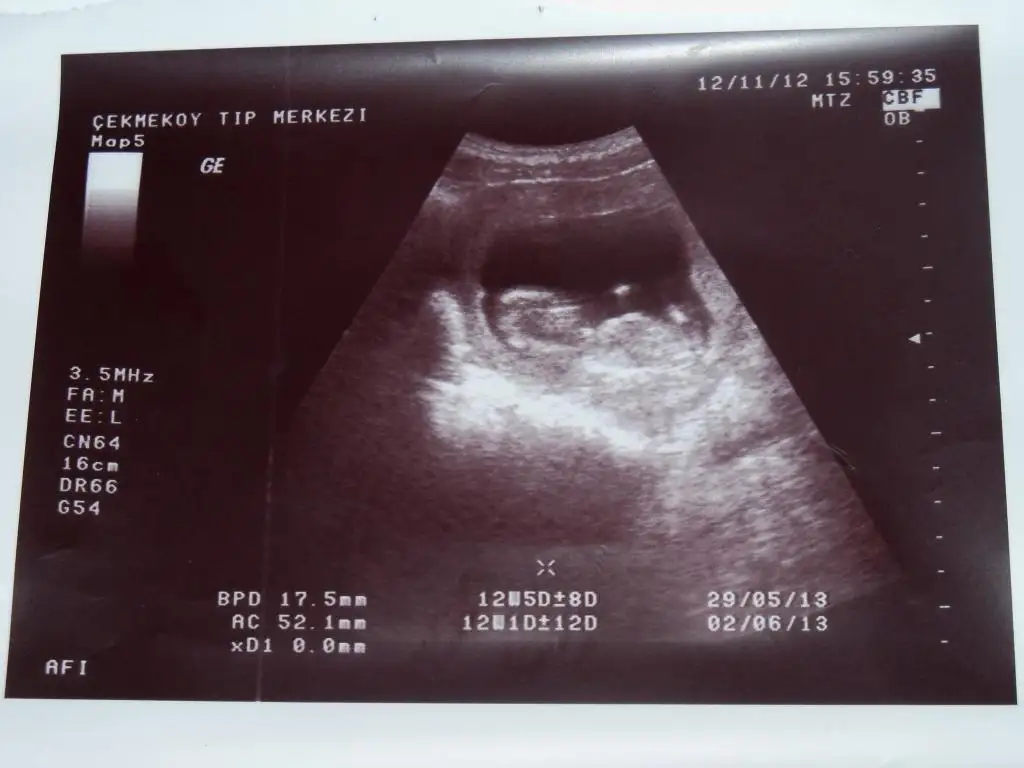

Eki Görüntüle 572552 Eki Görüntüle 572556 Eki Görüntüle 572559

bir tanesi 12+5 su en son ultrason goruntusunden ben hiç bişi anlamıyorum zaten neresi oldugunu

Solda kafasi var eli ve ayagi gozukuyor cnm nub yok su andaki resimde